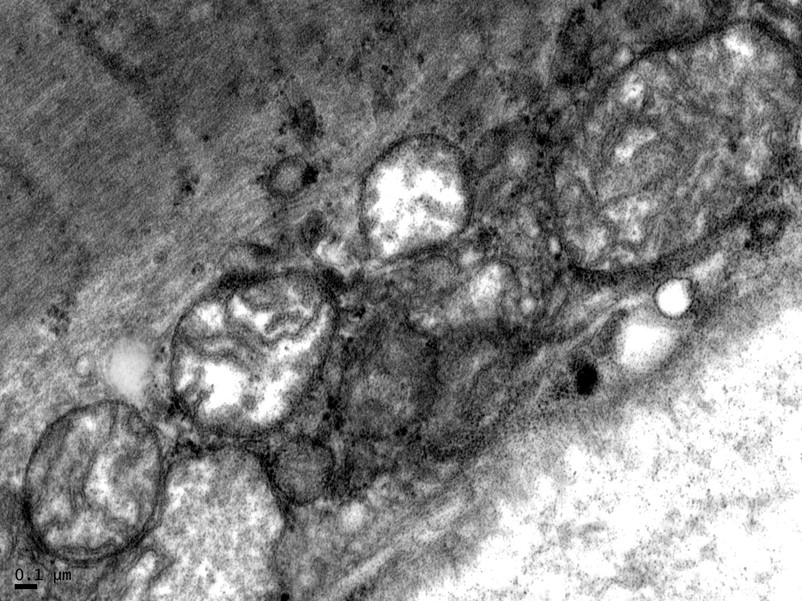

Muscle biopsy was performed, the results of which showed mildly increased and enlarged mitochondria on electron microscopy (Figure 4).

Figure 4. Muscle biopsy results showing enlarged mitochondria on electron microscopy.